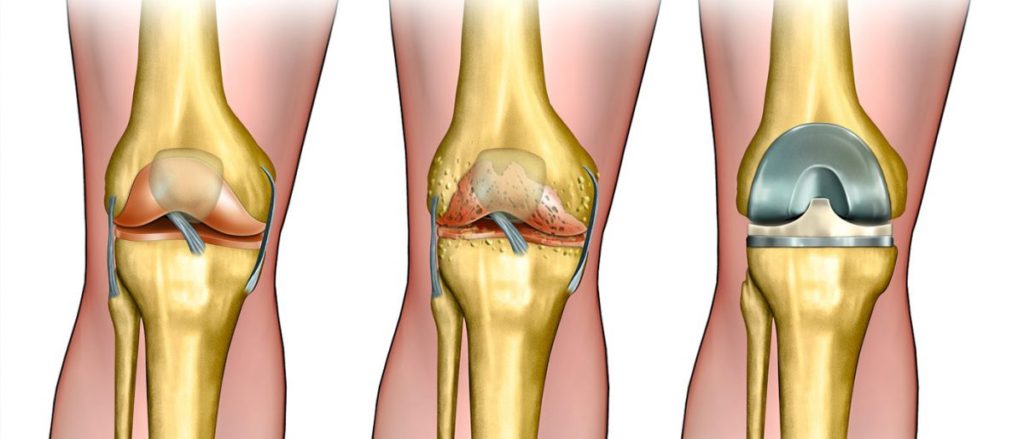

تهدف عملية استبدال مفصل الركبة الى علاج تآكل الغضروف في مفصل الركبة، الذي يحدث غالبا نتيجة لالتهاب المفاصل المزمن، على إختلاف أنواعه، خصوصا الفصال العظمي، الذي يؤدي الى تحديد قدرة المريض على تحريك مفصل الركبة، وتعتمد العملية على إستبدال المفصل المصاب بمفصل ركبة إصطناعي.

تزداد نسبة الاٍصابة بالفصال العظمي مع التقدم بالسن، حيث يحدث تضيق في الحيز المفصلي السليم، وتنكشف العظمة اٍلى تجويف المفصل، مع مرور الوقت تظهر آلام كثيرة، تصلب مفصلي وتقييدات ملحوظة في الحركة، والتي لا تتيح للرجل بأن تتحرك بشكل سليم أثناء المشي. يتم اٍجراء هذه العملية للمرضى الذين لا تتحسن حالتهم بمساعدة العلاج المحافظ (ممارسة الرياضة، المعالجة الفيزيائية أو استخدام الأدوية المضادة للاٍلتهاب)، وعندما لا يكون بوسع المريض مزاولة نشاطاته اليومية، مما يؤثر سلبا على جودة حياة المريض.

بعد إجراء تعقيم شامل لمنطقة العملية، يتم اٍحداث شق بطول 8-12 سم في الجزء الأمامي من الركبة، عند كشف الحيز في مفصل الركبة، يقوم الجراح باخراج الأنسجة الغضروفية والعظمية الزائدة، التي تؤثر سلبا على الحيز في مفصل الركبة.

يتم تعديل أسطح المفصل بحيث تستطيع احتواء المفصل الاصطناعي المركب من البلاستيك والمعدن، يتم الصاق المفصل الاصطناعي بعظمة الفخذ، الساق والرضفة، بواسطة مادة ملاطية أو مادة أخرى، تستعمل كمادة لاصقة فسيولوجية.

يتم تثبيت المفصل الاصطناعي الى عضلات الركبة والأربطة الداعمة للمفصل، من أجل الحصول على أداء حركي في المفصل بشكل مماثل للوضع الطبيعي. يتكون الجزء الملتصق بعظمة الفخذ من معدن صلب وأملس، والذي يستطيع تحمل أوزان ثقيلة. يتم تغطية المفصل بضمادة مرنة.

تختلف مفاصل الركبه الصناعيه في تصميمها و انواعها حسب احتياج المريض و حالته، الهدف عموما من مفاصل الركبه الصناعيه هو استبدال سطح الركبة المتآكل باخر صناعي، املس يمنع الالام الناتجه عن خشونه الركبه و يجعل حركه الركبه مرنة ليتمكن المريض من المشي بسهولة مرة أخرى.

ببساطه المفصل مكون جزئين مصنوعين من سبيكة معدنية تتحمل الضغوط والأحمال لمدة سنوات طويلة.

تثبت القطعتين على الأجزاء المساهمة في مفصل الركبة من أسفل عظمة الفخذ وأعلى عظمة القصبة.

تثبت بين السطحين المعدنيين قطعة مصنوعة من اللدائن البلاستيك وتسمح هذه القطعة بالحركة بنعومة ويسر.

هناك أنواع مختلفة من المفاصل منها المفاصل ذات السطح غير المتحرك وأخرى ذات سطح متحرك تسمح بحركة دوران القصبة للداخل والخارج مما يتيح حركة أكثر انسيابية ويطيل عمر القطعة البلاستيكية في المفصل، كما تختلف مدة عملية تغيير مفصل الركبة كما يوجد أنواع مفاصل للركبة ذات مفصل محوري في المنتصف يستخدم في الحالات التي تعاني من عدم ثبات واضح بسبب مشاكل بالأربطة المحيطة للركبة.

كما يوجد نوع من مفاصل الركبة يكون نصف مفصل فقط ويستخدم في حالات تآكل جهة من مفصل الركبة دون الأخرى، قد يحتاج الجراح مكونات إضافية مثل مكعبات معدنية لتعويض نقص في سطح المفصل أو كتركيب جزء إضافي لتعويض سطح عظام الصابونة الخلفي.

هناك أيضا أنواع من مفاصل الركبة الصناعية تحتاج للحفاظ علي الرباط الصليبي، أثناء الجراحة و أخرى تحتاج لاستئصاله أثناء الجراحة، يتم الكشف علي المريض وعمل إشعات خاصة لتحديد نوع المفصل المناسب لكل حالة.